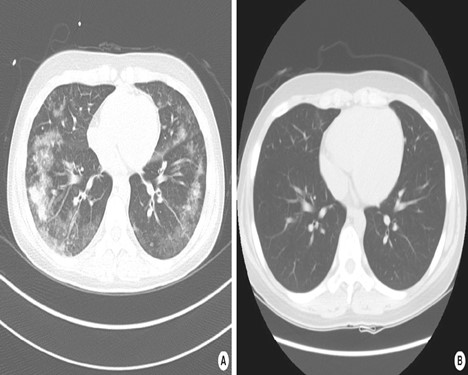

HRCT: Overlappende fund i forhold til røntgen af thorax. Der kan desuden ses interlobulær septal fortykkelse, bilateral matglastegning, konsoliderede infiltrater, fortykkede bronkosvaskulære bundter, centrilobulære noduli, konsolidering af luftveje samt evt. pleuraeffusion (se Figur 2).

Figur 2: Patient med akut eosinofil pneumoni. Ved indlæggelse (A), og ved opfølgning efter 8 uger (B). Med tilladelse fra patient.